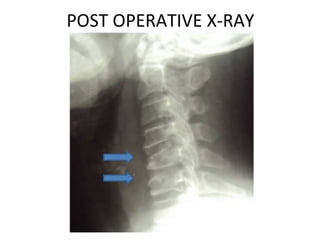

POST OPERATIVE X-RAY

Post operative image The patient had an ACDF at C4/C5 and C5/C6. The kyphosis is corrected and hopefully will be maintained until fusion in the hard collar.  She will wear the collar for 3 months.

Surgery performed was an anterior cervical discectomy and fusion using the patients’ iliac bone.  I decided to fuse at two levels C4/C5 and C5/C6 though the main focus was really to do a good decompression of the space behind the C5/C6 disc, which is the site of maximal compression on the MRI scan.

Surgery performed wasan anterior cervical discectomy and fusion using the patients’ iliac bone. I decided to fuse at two levels C4/C5 and C5/C6 though the main focus was really to do a good decompression of the space behind the C5/C6 disc, which is the site of maximal compression on the MRI scan.

Post operative imageThe patient had an ACDF at C4/C5 and C5/C6. The kyphosis is corrected and hopefully will be maintained until fusion in the hard collar. She will wear the collar for 3 months.